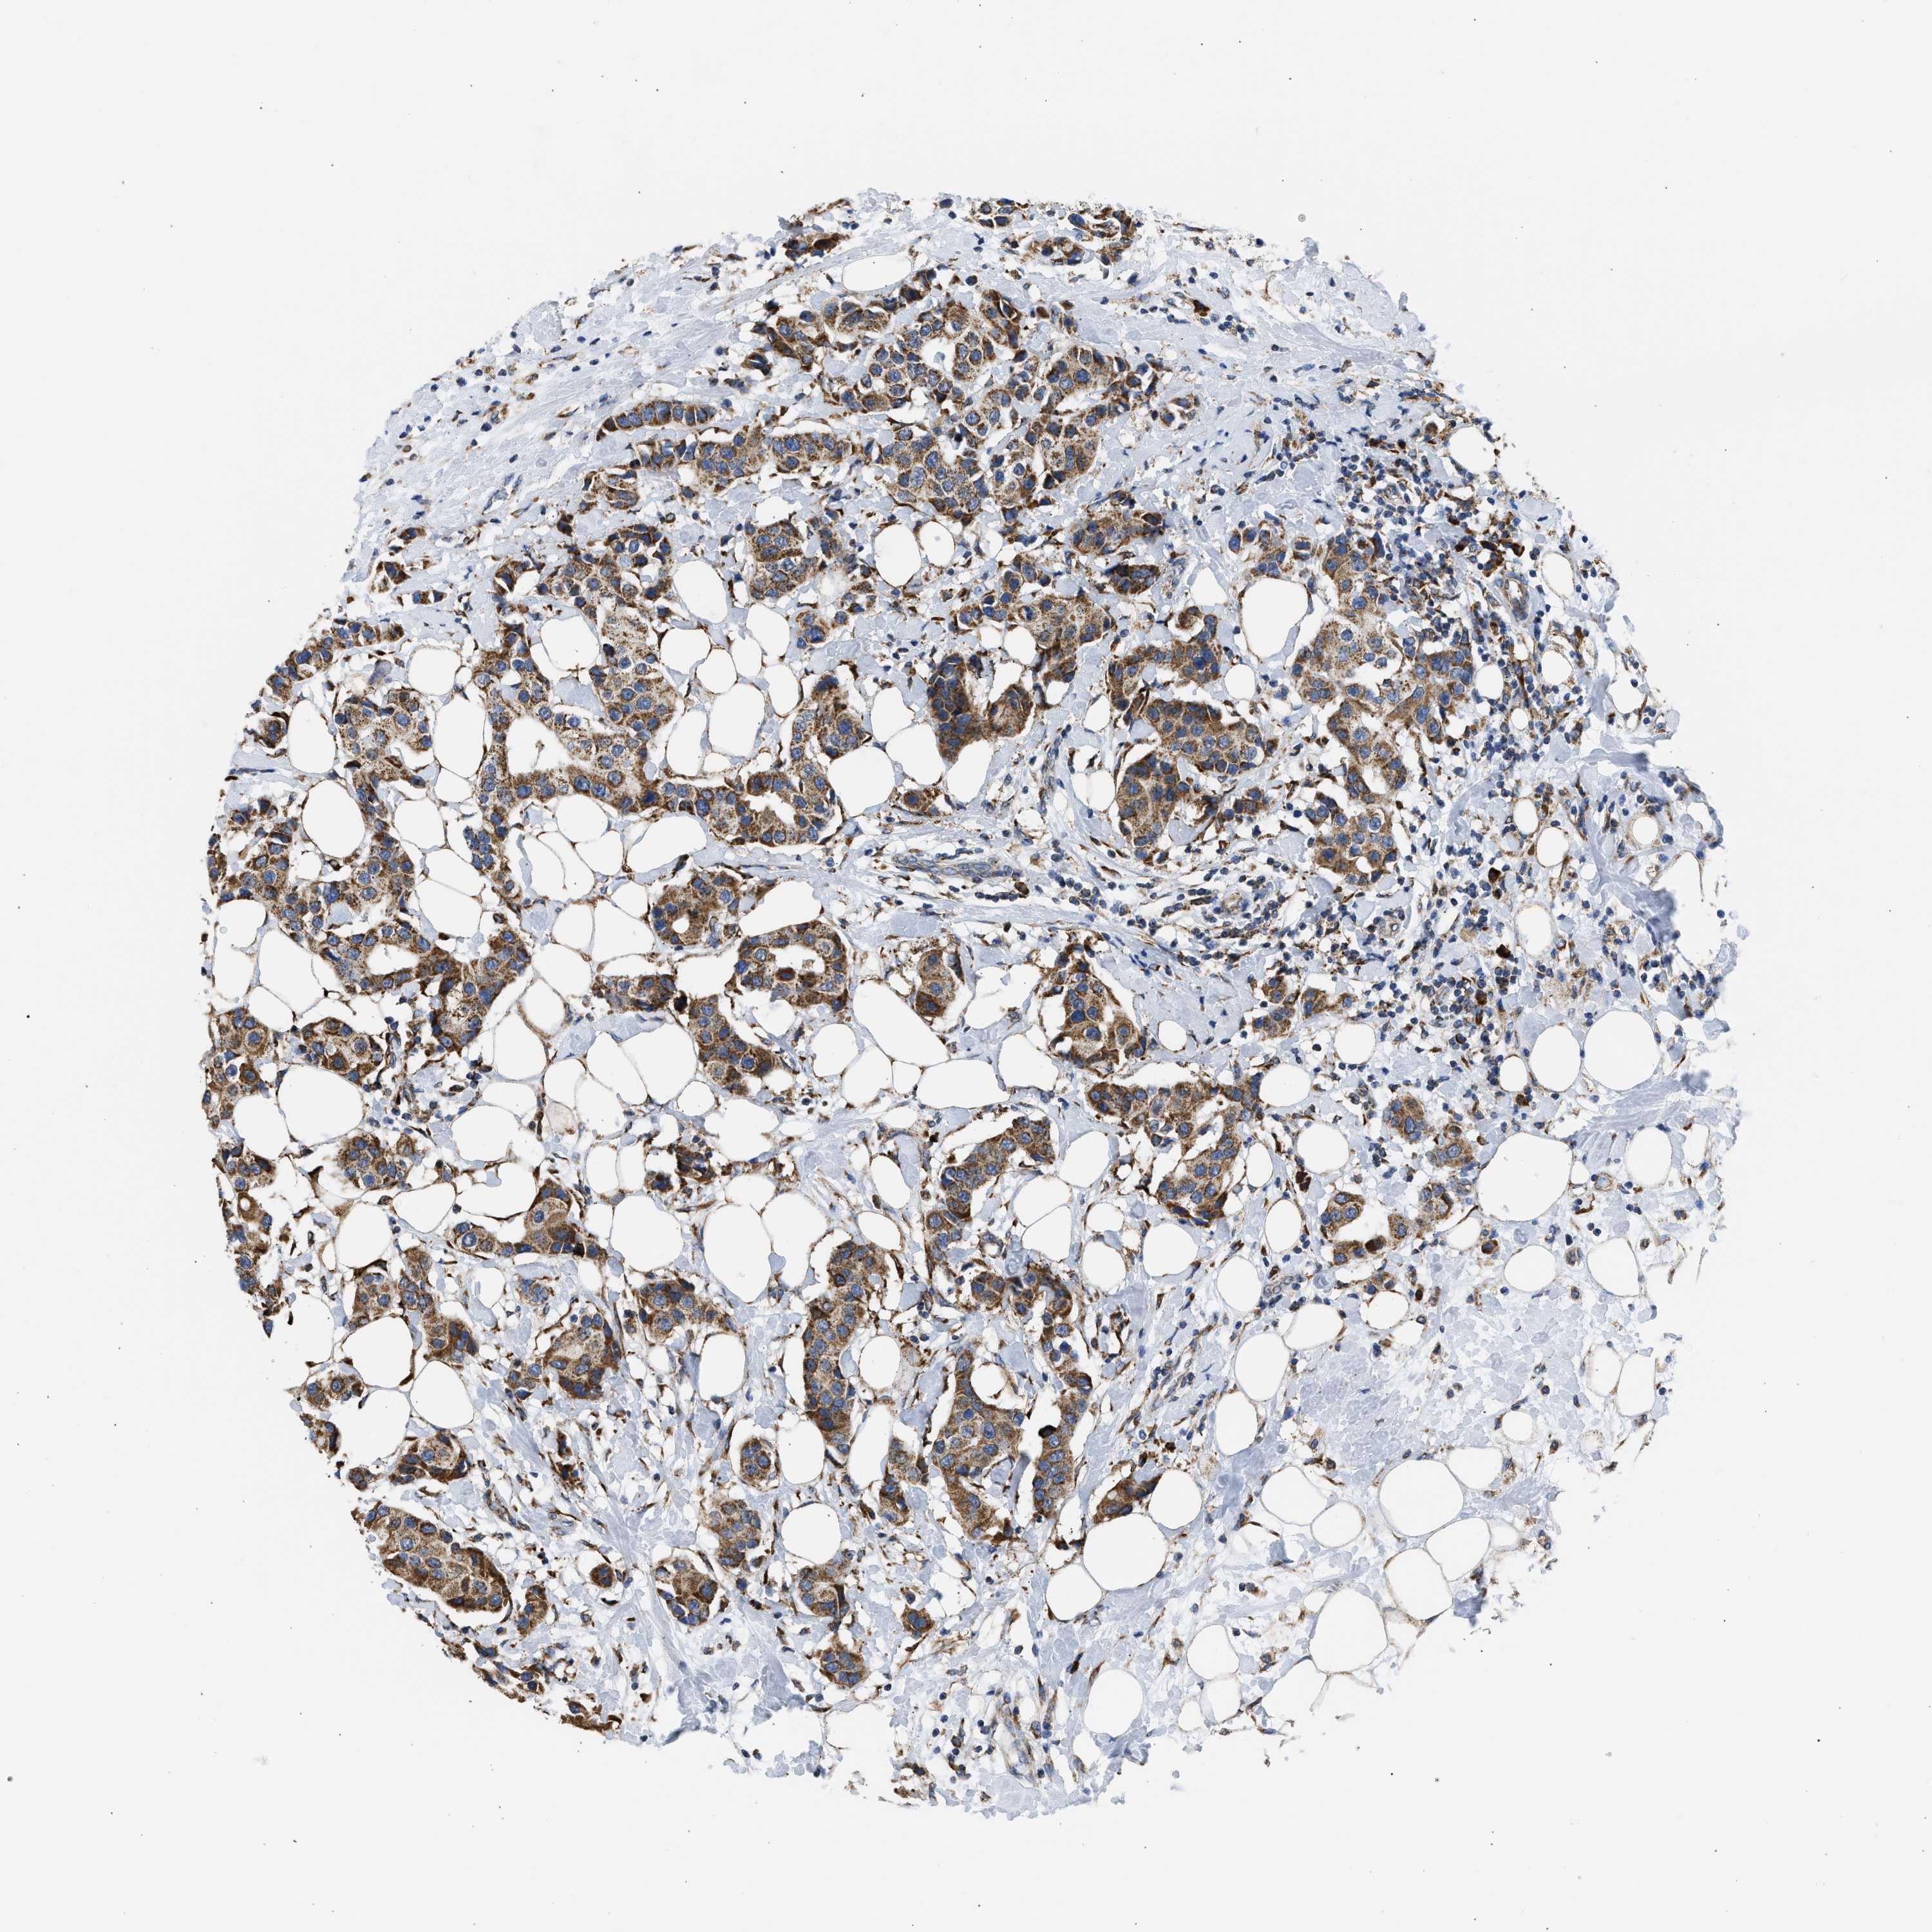

CANCER BREAST CANCER Show tissue menu

BRCA TCGA BRCA VALIDATION PROTEIN EXPRESSION

ANTIBODIES

AND

VALIDATION